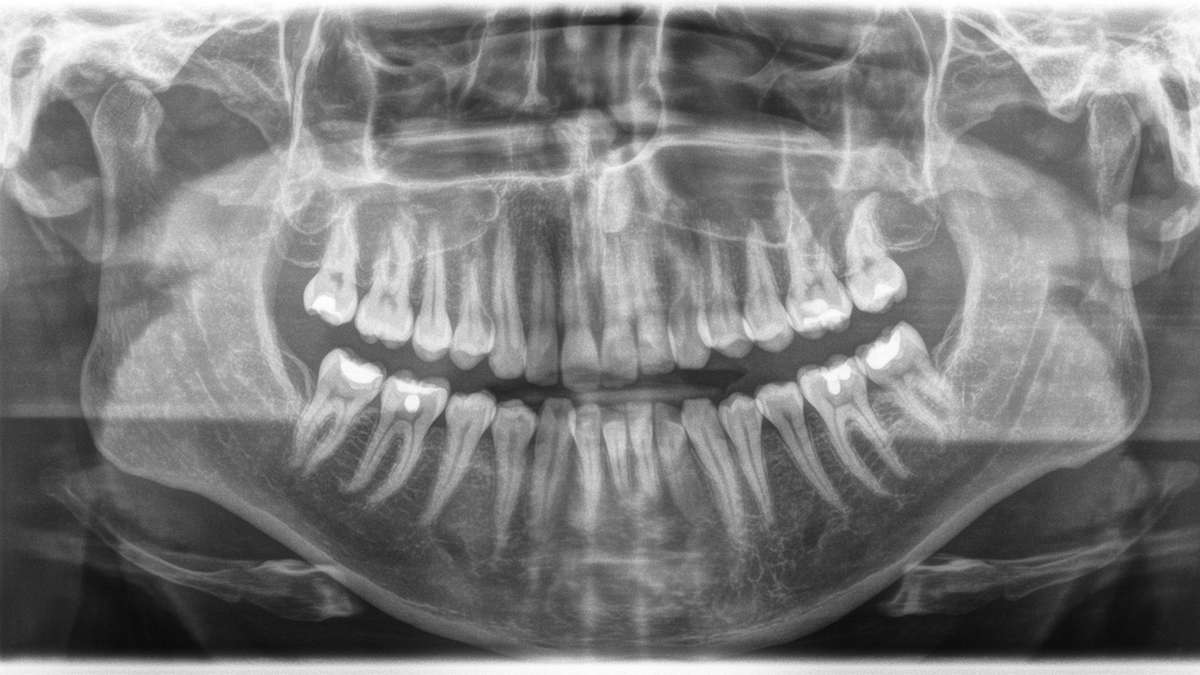

Gallery of Sample 2D Panoramic Images

Prophylactically treated full dentition. Wisdom teeth are not present. Large maxillary sinuses are visually inconspicuous. The adjacent anatomical structures are also radiographically inconspicuous.